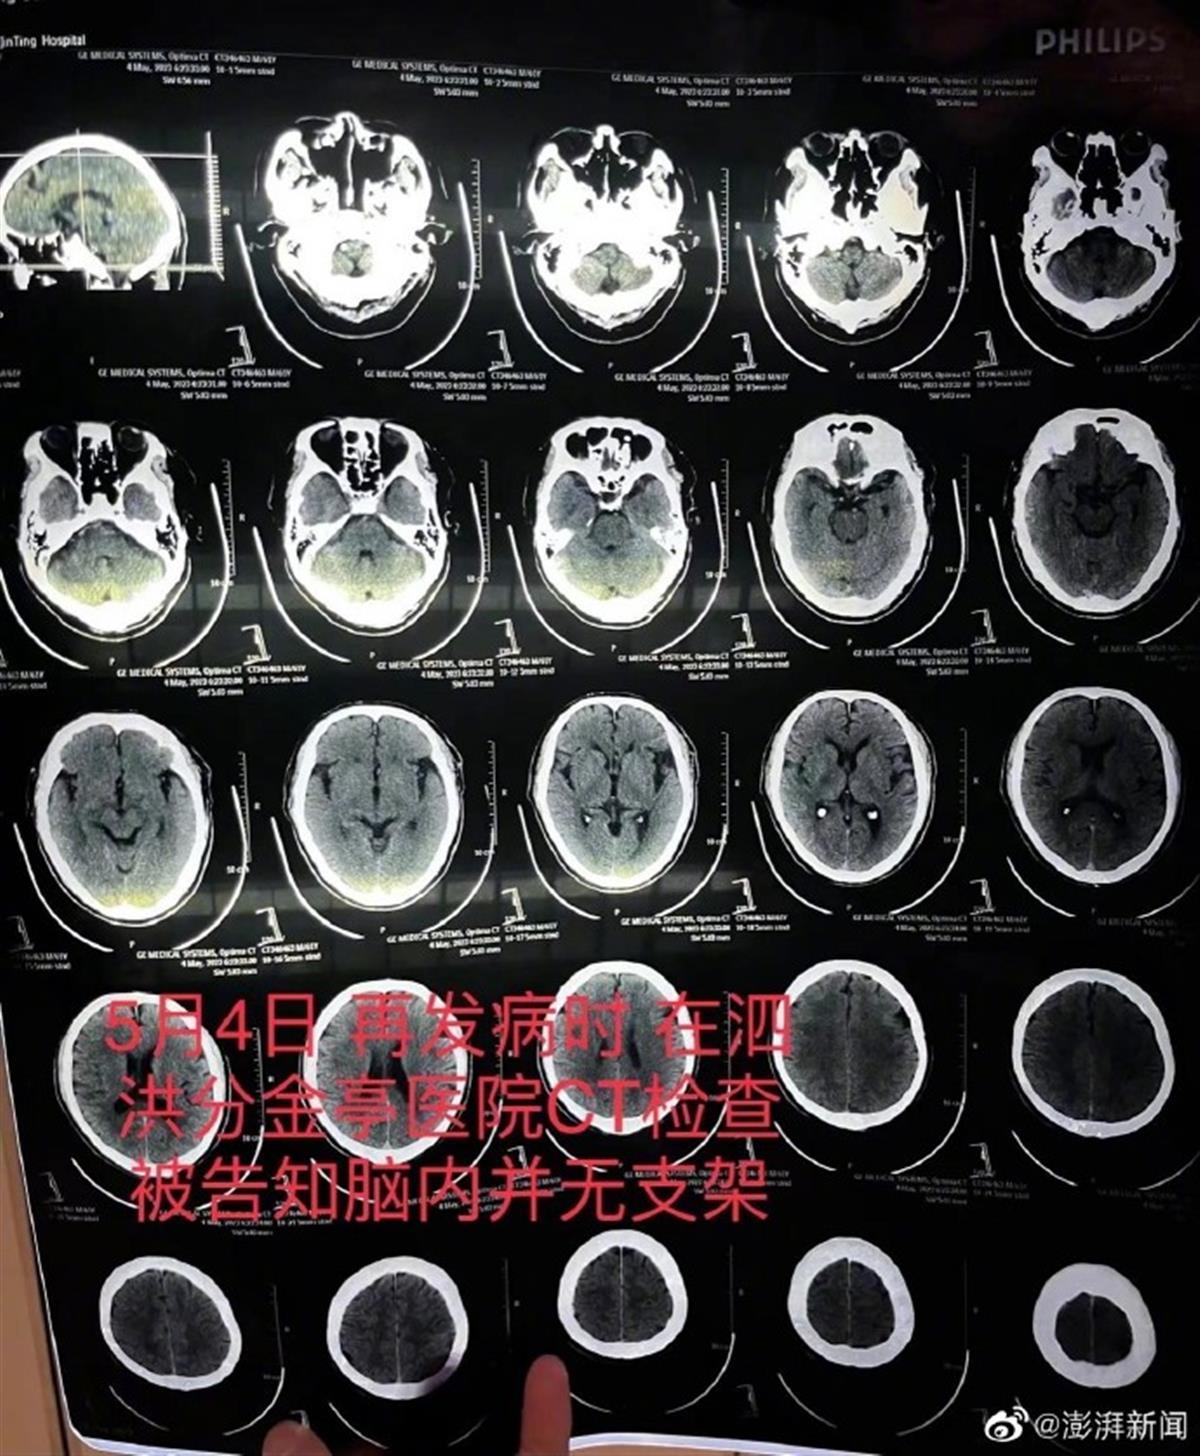

因父亲突发严重脑梗症状送医抢救,朱先生才发现,不久前医生称成功植入父亲颅内血管的高价进口支架竟然“消失”了。

图源:澎湃新闻